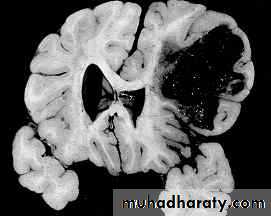

c. Intracerebral Haematoma

This is the least common of traumatic haematoma.They are due to areas of traumatic contusion coalescing into a contusional haematoma.

Disrupted cerebral tissue release thromboplastins that potentiate haemorrhage.

CT scan: appear as hyperdence lesions with associated mass effect and midline shift.Large intracerebral haematomas should be evacuated unless the patient’s neurological state is improving.

Small inracerebral haematomas may not require removal, but be aware that they can expand.